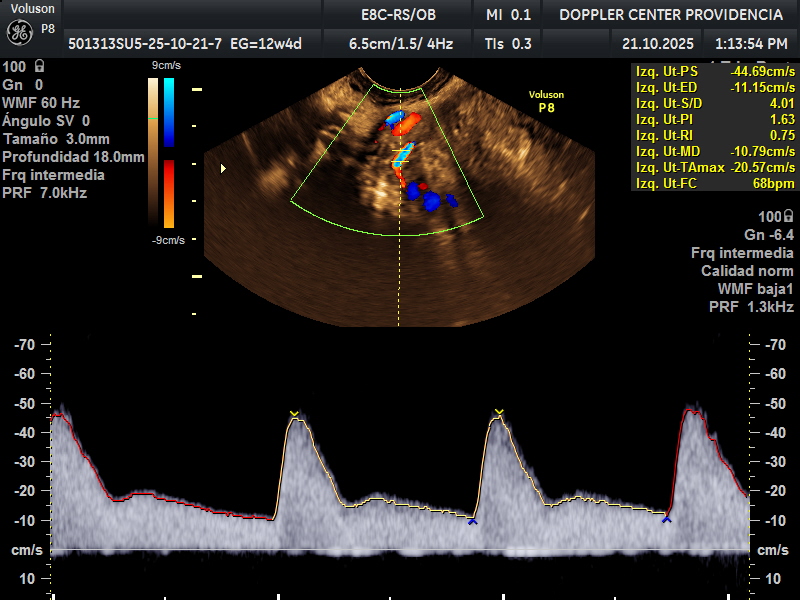

Es una técnica especializada de ultrasonido que utiliza el efecto Doppler para evaluar el flujo sanguíneo en el sistema circulatorio del feto y la madre durante el embarazo.

Se usa principalmente para evaluar el flujo sanguíneo en la placenta, el cordón umbilical y los vasos sanguíneos de la madre y el feto. Esto proporciona información valiosa sobre la salud del embarazo y la circulación fetal.